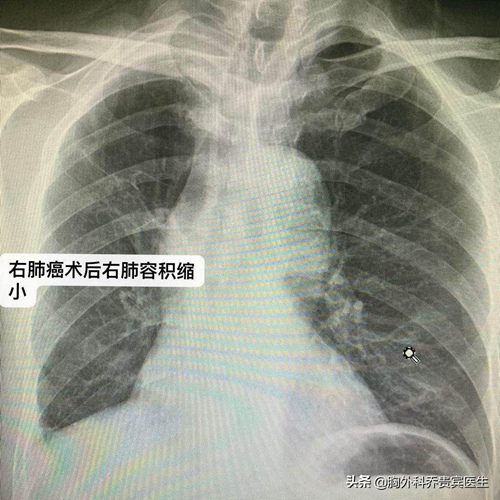

这是一位64岁的老年男性,性格开朗乐观,很喜欢抽烟、喝酒。老人5年前因为咳嗽、咳痰,发现右上肺有个肿块,我给他做了肺癌根治手术。当时老人承诺得好好的,术后就戒烟戒酒,哪知,术后恢复很好,老人又开始抽烟、喝酒。

老人在女儿的陪同下,找到我,还是希望我来帮他手术。术前为老人进行了全身检查,幸好未发现转移。